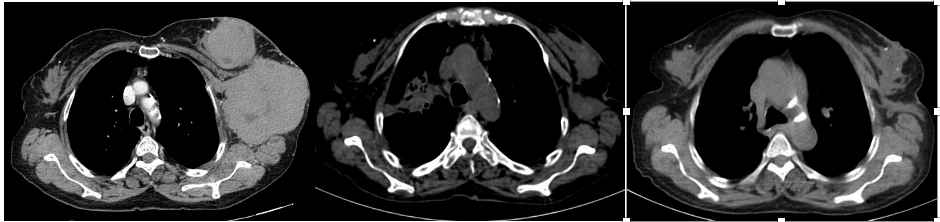

Mammography (Figure 1)revealed a large, round, well circumscribed, high density mass in upper outer quadrant and central region, measuring 7 x 6 cm. No suspicious calcification, architectural distortion, nipple retraction, skin or nipple-areolar thickening was seen. Associated was a large node measuring 11 x 9 cm noted in the left axillary region. Right breast and axilla were unremarkable. Correlation USG images were not available on Electronic Medical Record and PACS system, hence not available for reproduction here, however, as per the report, it appeared as a lobulated hypoechoic mass in left breast with necrotic changes, and internal vascularity in the solid component. Similar morphology additional left axillary mass was also seen. Imaging features highlighted the absence of spiculation, calcification, architectural distortion, irregular margins. The mass was categorized as BIRADS 4c, with a high probability of malignancy.Differentials on basis of mammography and USG were triple negative breast carcinoma, phyllodes tumor, cellular fibroepithelial lesion, organized abscess, lymphoma or metastases. CT was done to see disease extent which revealed a heterogeneously enhancing left breast mass (Fig 2a), large axillary and retropectoral adenopathy. No other adenopathy or abnormality seen. Biopsy from the breast lump was performed which showed Non-Hodgkin’s lymphoma of diffuse large B cell type, positive for CD20 and Mum1 which are markers of mature B cells. CSF study and Bone marrow aspiration were negative for involvement by disease. Diagnosis of primary breast lymphoma was made and planned for chemotherapy R-CEOP (rituximab, cyclophosphamide, etoposide, vincristine and prednisone) followed by IFRT (Involved field radiotherapy). Post 3 cycles of chemotherapy, FDG PET (Fig 2b and 3a) was done which showed significant reduction in size of breast mass and axillary node, breast mass then measuring 2 x 2cm with SUVmax of 7 while the axillary node measured 3.4 x 2.6 cm with SUV max of 3.7. Another repeat FDG PET Scan (Fig 2c and 3b)was done after completion of chemotherapy for further response assessment which showed no FDG uptake in left breast lesion suggesting complete metabolic response however size of the lesion appeared nearly stable, as compared to previous FDG PET (performed in the interim period of therapy). Patient has a 2-year disease free interval, and has not visited due to the Covid pandemic situation, but on telephonic follow up, is asymptomatic with good performance status. Figure 4: Low power (a), High power (b) and CD20 staining (c) from another case of primary breast lymphoma. These are representative images added here for teaching purpose. Figure 2a (10x power) shows diffuse infiltration by malignant cells. Figure 2b shows monomorphic round cells with apoptosis. Figure 2c staining positive for phenotype analysis for B cells. Representative USG image (Figure 5 and 6) of different patients with biopsy proven B cell lymphoma with different demographics. (Figure 5) USG of breast lump in a 56 year old woman shows hypoechoic, round mass, circumscribed margin with posterior acoustic enhancement mimicking a receptor negative carcinoma, mucinous carcinoma or fibroepithelial lesion. (Fig 6) Large mass in a 21 years old lady shows mixed echogenicity oval mass of parallel orientation, with well circumscribed margin and surrounding echogenic rim due to edema, mimicking a phylloides tumour, a fibroepithelial lesion or a malignant etiology.